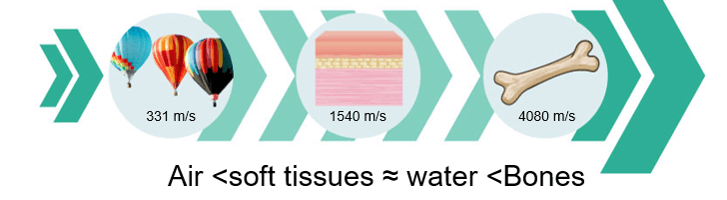

Propagation Speed

Theoretically, the speed of propagation is the speed at which sound travels through a particular organ and is dependent on the elastic property and density of the organ. The harder the tissue, the faster the speed of propagation. The average speed of sound in soft tissues such as the chest wall and the heart is 1,540 meters per second.